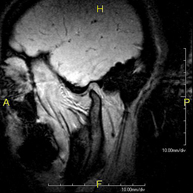

Prova diagnòstica no invasiva que consisteix en l'obtenció d'imatges d'alta definició anatòmica de la hipòfisi cerebral mitjançant l'ús d'un camp electromagnètic i ones de ràdio (amb un emissor i un receptor). No utilitza radiació ionitzant. Indicacions: trastorn del creixement, trastorns hormonals, tumors. - RM de Sins paranasals

Prueba diagnóstica no invasiva que consiste en la obtención de imágenes de alta definición anatómica del cráneo mediante el empleo de un campo electromagnético y ondas de radio (con un emisor y un receptor). No utiliza radiación ionizante. En ocasiones se deberá emplear contraste paramagnético (Gadolinio) para completar el estudio. - RM Cuello